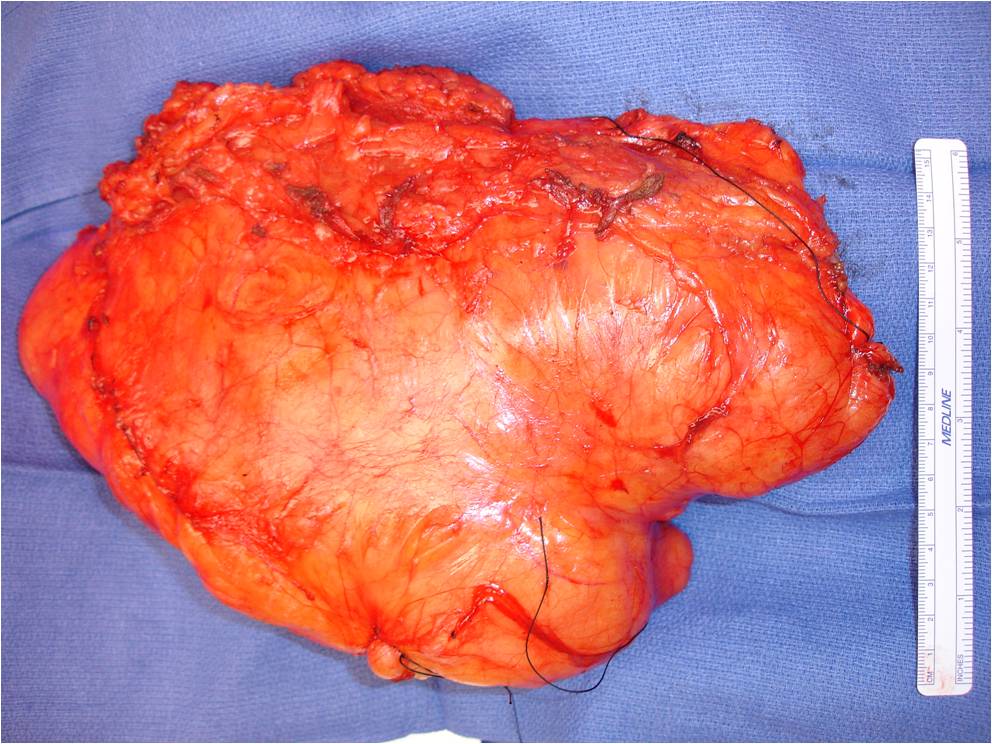

PATHOLOGY

Gross

• Soft yellow fatty mass indistinguishable from normal fat

• Well circumscribed

• Lobular growth in some lipomas

• May have a significant fibrous component reflected as white tissue

• Muscle fibers may be present with intramuscular lipomas